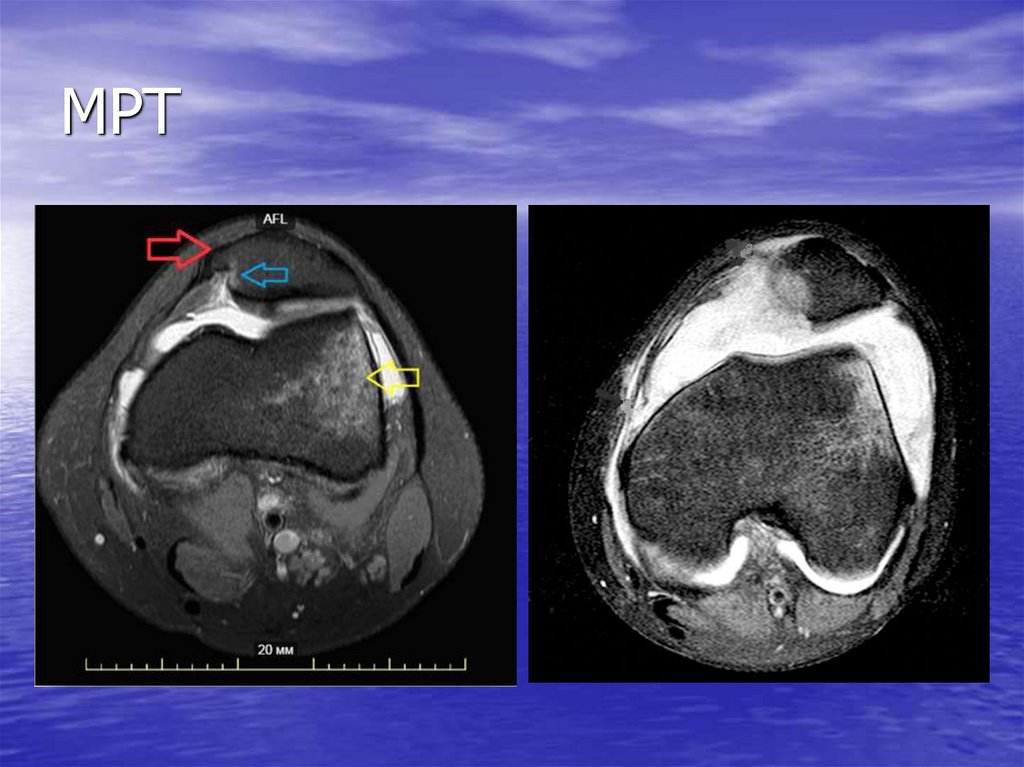

9. МРТ

РКТ